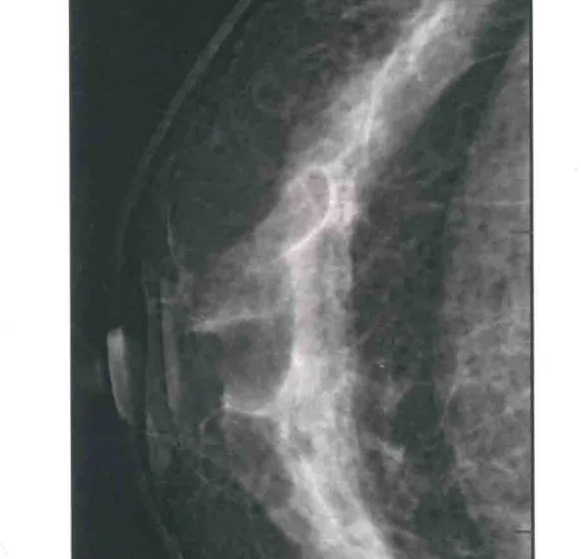

二、圖像顯示要求,含乳腺的基底部及內外側乳腺組織,需要顯示胸肌前緣或胸壁。頭尾位與內外斜位乳頭後線長度差≤1厘米;顯示實質後的乳腺組織,乳頭位於切線位,乳腺組織重疊;雙側乳腺頭尾位照片相對放置,則兩側乳腺呈球形;影像密度和對比度良好,能顯示0.1毫米細小鈣化,清晰沒有偽影異物、運動偽影和切割偽影等。